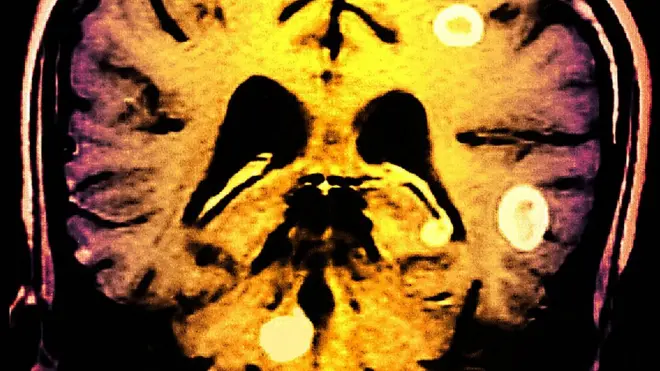

El extraordinario caso de una mujer que le extirparon medio cerebro porque sufría encefalitis de Rasmussen

Poco después los médicos le diagnosticaron con una enfermedad rara: encefalitis de Rasmussen.

Se caracteriza por crisis en el sistema locomotor, epilepsia parcial continua y deterioro neuropsicológico progresivo, con alteraciones cognitivas y lingüísticas.

Los doctores dijeron a sus padres que el mejor tratamiento era extirpar la mitad del cerebro, ya que decían que a esa temprana edad el cerebro se reajusta solo.